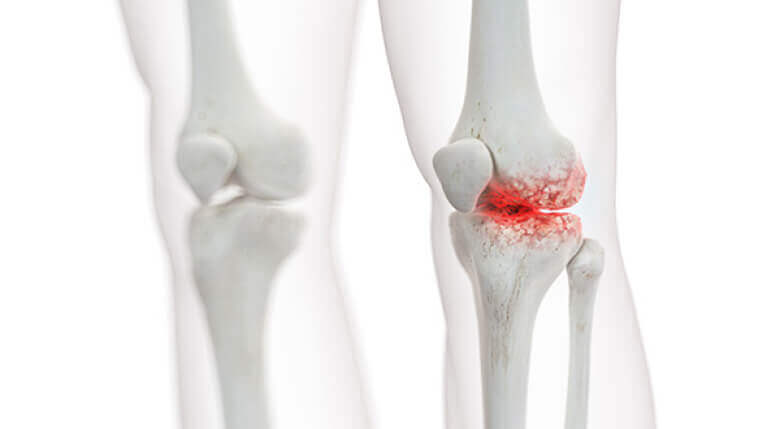

इन सभी दवाओं का, चाहे वे दर्द को कितना भी कम करें, जोड़ो का इलाज नहीं होता। ये केवल लक्षणों को छिपाती हैं, लेकिन समस्या को हल नहीं करतीं, जो कि ओस्टियोफाइट्स के संचय में हैकैल्सीफाइड नमक, जो जोड़ो, उपास्थि और उनके आसपास के ऊतकों को नुकसान पहुंचाते हैं

ओस्टियोफाइट्स नमक के क्रिस्टल होते हैं, जो रेत जैसे कागज की तरह जोड़ो को घिसते हैं, जिससे तीव्र दर्द, सूजन और सूजन होती है।

अगर लक्षणों को दबाया जाता रहता है, तो ये नमक के क्रिस्टल जमा होते रहते हैं, जिससे जोड़ का विनाश होता है और वह पूरी तरह से निष्क्रिय हो सकता है

📌यहां स्पष्ट रूप से देखा जा सकता है कि नमक ने गलत उपचार के कारण जोड़ को पूरी तरह से नष्ट कर दिया।

यहां स्पष्ट रूप से देखा जा सकता है कि नमक ने गलत उपचार के कारण जोड़ को पूरी तरह से नष्ट कर दिया। कुछ ही समय में, बड़े टुकड़े ओर्थोसोले को आसानी से हड्डी का बड़ा हिस्सा तोड़ सकते थे, जिससे राजेश को जोड़ के पूरी तरह से खराब होने और स्थायी विकलांगता का सामना करना पड़ता।